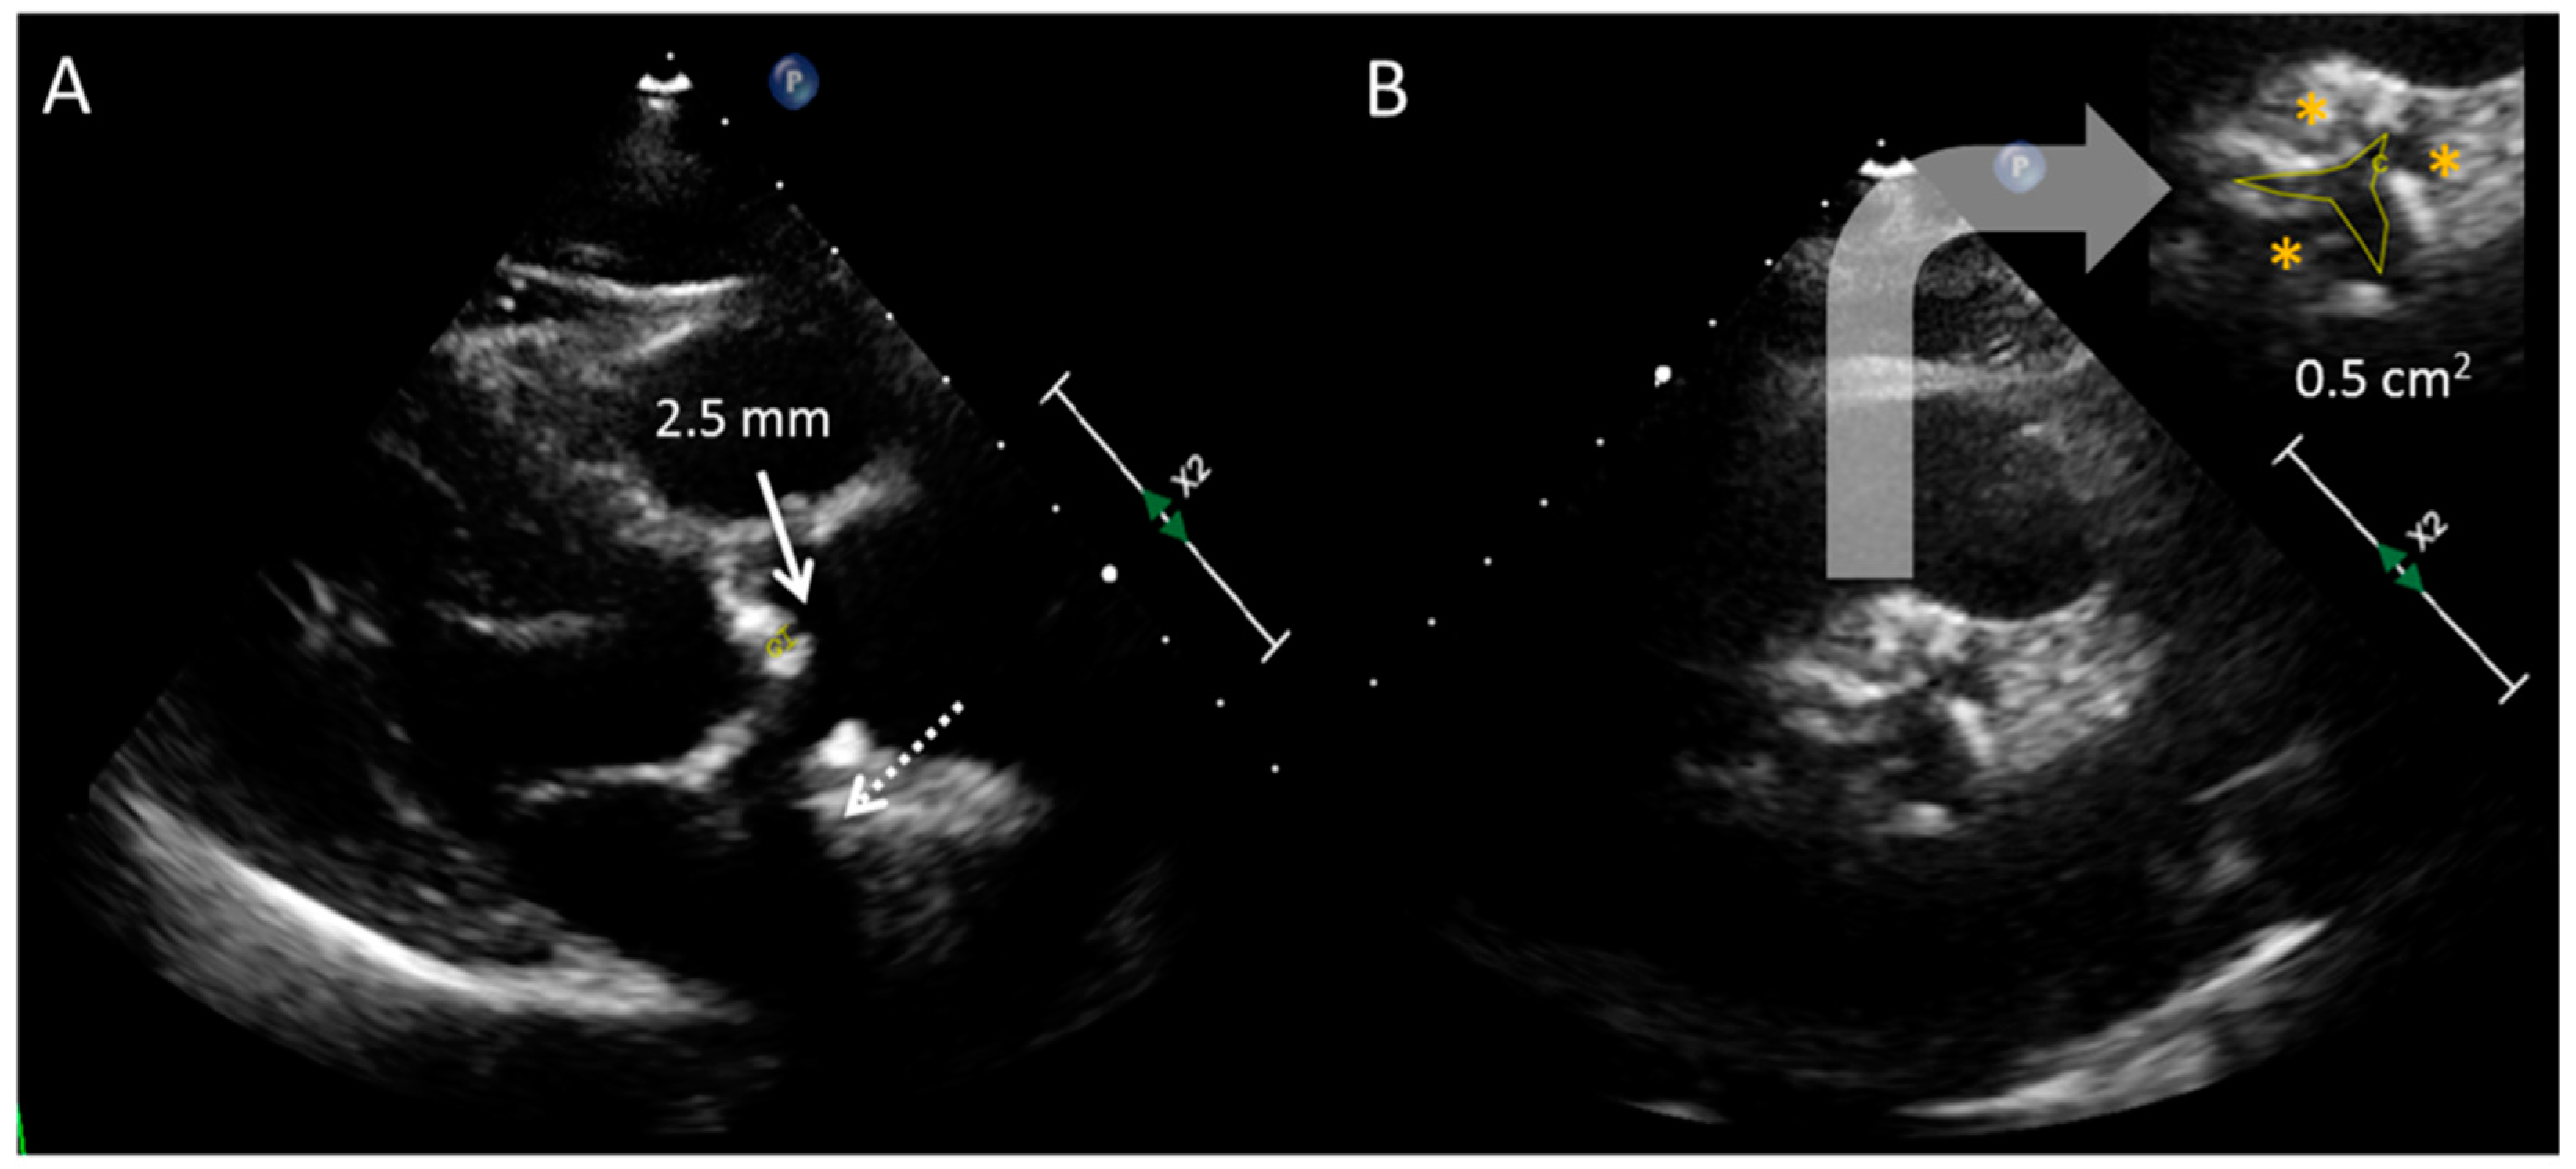

2.2. Transesophageal Echocardiography